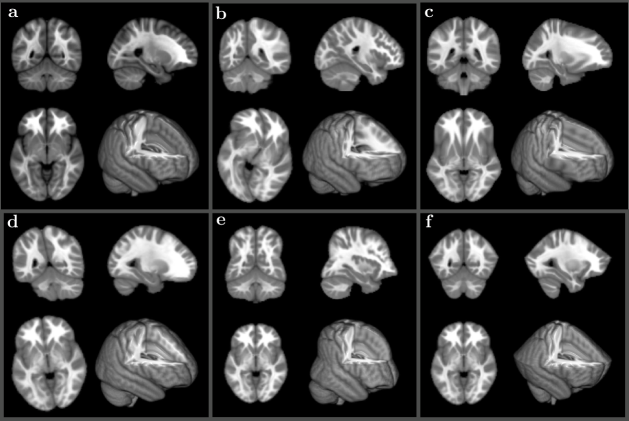

Refer to caption

Fig 2: Results of high resolution anatomical (HRA) mapping to the same anatomical reference volume (shown in a). (b) Central planes for four volumes out of ten subjects used for mapping. (d) Residual images of SWD preconditioning (fitted with orthogonal transform) for the same four volumes, (c) all ten volumes averaged. Residual images of symplectomorphic transforms using 5 (f) and 15 (h) embedded shells with all ten subject averages in (e) and (g) respectively. (i) Convergence plots of the same four subjects as a function of a number of shells. (j) Illustrative plots of curvilinear grids for the same four subjects, using blue color for the anterior-posterior grid lines, green for the dorsal-ventral grid lines, and red for the right-left lateral grid lines.

Figure 2 shows the collage of images related to this registration test. The central plane from anatomical volume used as reference is shown in (a) panel. The same location planes for randomly selected four volumes out of ten subjects are shown in (b). Panel (d) shows the result of SWD preconditioning step equivalent to rigidly fitting each volume to reference with orthogonal transform that includes rotation and uniform scaling for the same four volumes. Panel (c) shows image obtained by averaging of SWD preconditioned volumes for all ten subjects. The next four panels show results of symplectomorphic transforms using 5 (f) and 15 (h) embedded energy shells again with correspondent all subject averages in (e) and (g) respectively. And finally, panel (i) show illustrative plots of curvilinear grids for the same randomly chosen four subjects.

Overall, as would be expected, the symplectomorphic registration shows significant improvement over rigidly fitted volumes, with additional improvement due to increase of a number of energy shells used in registration. In general, there is no obvious relationship between the number of shells and the accuracy, although practically, as the number of shells is determined by selected limits of Jacobian range (ϵitalic-ϵ\epsilon) (and indirectly can be affected by a selected policy of time step adjustments), symplectomorphic registration with increased number of shells may allow to obtain better overall accuracy. The total processing time for all ten subject fitting ranges from 15 to 40 minutes based on the selected quality (this is time measured by running the registration on 12 cores Intel® CoreTM i7-4930K CPU 3.40GHz).